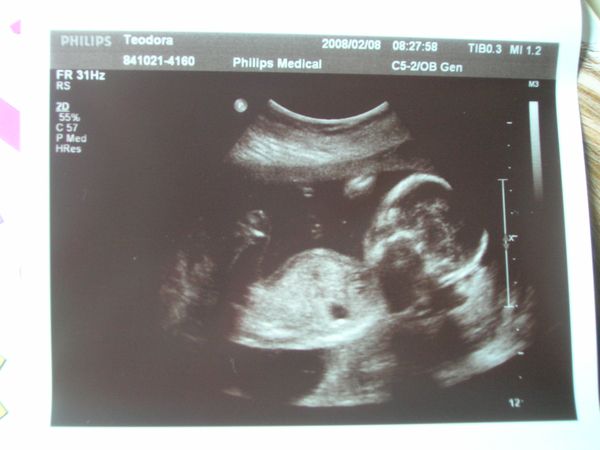

19. hét

19. hét2008.02.12 18:03